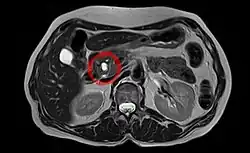

Sonografie, Computertomographie und Kernspintomographie sind die Diagnoseverfahren der Wahl. Aufgabe dieser Methoden ist, Krebserkrankungen von gutartigen Tumoren zu unterscheiden. Weiterhin ist zu erkennen, ob ein Tumor operabel ist. Dies entscheidet sich daran, ob Metastasen vorliegen und ob die dem Pankreas anliegenden Arterien (Arteria mesenterica superior, Truncus coeliacus, Arteria hepatica) von dem Tumor betroffen sind. Die Darstellung der Blutgefäße wird dabei in der Regel durch Gabe von Kontrastmitteln verbessert.